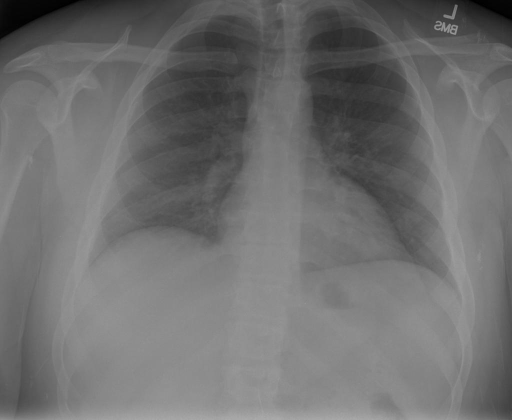

# 本文贡献 ![](./assets/images/xrayglm.png) - 借助ChatGPT以及公开的数据集,我们构造了一个`X光影像-诊断报告`对的医学多模态数据集; - 我们将构建的中文胸部X光片诊断数据集在[VisualGLM-6B](https://github.com/THUDM/VisualGLM-6B)进行微调训练,并开放了部分训练权重用于学术研究; # 数据集 - [MIMIC-CXR](https://physionet.org/content/mimic-cxr-jpg/2.0.0/)是一个公开可用的胸部X光片数据集,包括377,110张图像和227,827个相关报告。 - [OpenI](https://openi.nlm.nih.gov/faq#collection)是一个来自印第安纳大学医院的胸部X光片数据集,包括6,459张图像和3,955个报告。 在上述工作中,报告信息都为非结构化的,不利于科学研究。为了生成合理的医学报告,我们对两个数据集进行了预处理,并最终得到了可以用于训练的**英文报告**。除此之外,为了更好的支持中文社区发展,借助ChatGPT的能力,我们将英文报告进行了中文翻译,并最终形成了可用于训练的数据集。 |数据集|数量|下载链接| |:-|:-|:-| |MIMIC-CXR-zh|-|-| |OpenI-zh|6,423|[诊疗报告](./data/Xray/openi-zh.json) 、[X光影像](https://pan.baidu.com/s/13GBsDMKf6xBZBSHpoWH_EA?pwd=k9sh)| # 快速上手 1. 安装环境 ```bash # 安装依赖 pip install -r requirements.txt # 国内换源安装依赖 pip install -i https://mirrors.aliyun.com/pypi/simple/ -r requirements.txt ``` 此时默认会安装`deepspeed`库(支持`sat`库训练),此库对于模型推理并非必要,同时部分`Windows`环境安装此库时会遇到问题。 如果想绕过`deepspeed`安装,我们可以将命令改为: ```bash # 安装依赖 pip install -i https://mirrors.aliyun.com/pypi/simple/ -r requirements_wo_ds.txt # 安装SwissArmyTransformer pip install -i https://mirrors.aliyun.com/pypi/simple/ --no-deps "SwissArmyTransformer>=0.3.6" ``` 2. 模型推理 CLI推理: ```python python cli_demo.py --from_pretrained checkpoints/finetune-XrayGLM-05-25-01-04 --prompt_zh '详细描述这张胸部X光片的诊断结果' ``` 更多[参数](https://github.com/WangRongsheng/XrayGLM/blob/main/cli_demo.py#L16) # 效果展示 诊断: |X光影像|诊疗报告(医生)|XrayGLM| |:-|:-|:-| |![](./data/Xray/2_1.png)|根据X射线图像,心脏大小正常,肺部看起来很清晰。已经排除了肺炎、积液、水肿、气胸、腺病、结节或肿块的存在。该发现表明一切正常。换句话说,总体印象是胸部正常。|X光片显示,心脏大小正常。肺部没有气胸或胸腔积液的证据。骨骼结构看起来没有任何异常。总的来说,X光片表明没有发现急性心肺疾病的迹象。| |![](./data/Xray/2882_1.png)|X光图片显示没有扭曲的区域、可疑的骨质不透明度或胸腺积液。心脏大小轻微增大,但非常稳定。此外,没有气胸的证据,肺野也正常。总体来说,X光片显示没有急性心脏异常,但要注意轻微的心脏扩大。|X光片显示,心脏大小正常。肺部和纵隔轮廓清晰,没有气胸或胸腔积液的证据。骨骼结构完整,没有任何急性异常。| |![](./data/Xray/2577_1.png)|心影形态在正常范围内。没有急性骨质异常。有可能出现没有明显的吸水或肺实质状况的线索。没有大面积积液或气胸。有可能怀疑其有误吸或肺实质问题。为了确诊和治疗,可能需要进行适当的影像学随访。|心脏大小正常,肺部和纵隔轮廓清晰。没有急性异常或活动受限的证据。没有任何明显的气胸、胸腔积液或肺不张的迹象。此外,也没有发现任何局灶性骨质异常或其他急性疾病。| 多轮对话: |X光影像|诊疗报告(医生)| |:-|:-| |![](./data/Xray/861_1.png)|右侧主动脉突出观察到。心脏大小正常。胸部未发现明显的肺气肿、胸膜积液或可疑的肺部病变。报告指出已知右侧主动脉情况正常。| ```bash >> X光影像路径:./data/Xray/861_1.png >> 用户:这是一张什么图? >> XrayGLM:这张图片显示的是一张肺部检查的X光片。 >> 用户:请描述这张胸部X光片的诊断结果 >> XrayGLM:心脏大小正常,肺部清晰。没有急性心肺疾病的证据。 >> 用户:是否存在肺气肿? >> XrayGLM:没有肺气肿。心脏大小正常,肺部清晰。没有发现急性心肺疾病的证据。 >> 用户:平时饮食该注意什么? >> XrayGLM:饮食应该健康,均衡。建议增加蛋白质的摄入量,因为蛋白质有助于维持肌肉和骨骼的健康。多食用蔬菜、水果、全谷物以及健康的脂肪来源如橄榄油、鱼类等可以帮助获得足够的维生素和矿物质。此外,避免过度饮酒或吸烟,这些习惯可能会对心脏健康产生负面影响。 ``` # 项目致谢 1. [VisualGLM-6B](https://github.com/THUDM/VisualGLM-6B)为我们提供了基础的代码参考和实现; 2. [MiniGPT-4](https://github.com/Vision-CAIR/MiniGPT-4)为我们这个项目提供了研发思路; 3. ChatGPT生成了高质量的中文版X光检查报告以支持XrayGLM训练; 4. [gpt_academic](https://github.com/binary-husky/gpt_academic)为文档翻译提供了多线程加速; 5. [MedCLIP](https://github.com/RyanWangZf/MedCLIP) 、[BLIP2](https://huggingface.co/docs/transformers/main/model_doc/blip-2) 、[XrayGPT](https://github.com/mbzuai-oryx/XrayGPT) 等工作也有重大的参考意义; ![](./assets/images/mpu.png) 这项工作由[澳门理工大学应用科学学院](https://www.mpu.edu.mo/esca/zh/index.php)硕士生[王荣胜](https://github.com/WangRongsheng) 、[段耀菲](https://github.com/IsBaSO4) 、[李俊蓉](https://github.com/lijunrong0815)完成,指导老师为檀韬副教授、[彭祥佑](http://www.patrickpang.net/)老师。 *特别鸣谢:[USTC-PhD Yongle Luo](https://github.com/kaixindelele) 提供了有3000美金的OpenAI账号,帮助我们完成大量的X光报告翻译工作 # 免责声明 本项目相关资源仅供学术研究之用,严禁用于商业用途。使用涉及第三方代码的部分时,请严格遵循相应的开源协议。模型生成的内容受模型计算、随机性和量化精度损失等因素影响,本项目无法对其准确性作出保证。即使本项目模型输出符合医学事实,也不能被用作实际医学诊断的依据。对于模型输出的任何内容,本项目不承担任何法律责任,亦不对因使用相关资源和输出结果而可能产生的任何损失承担责任。 # 项目引用 如果你使用了本项目的模型,数据或者代码,请声明引用: ```bash @misc{wang2023XrayGLM, title={XrayGLM: The first Chinese Medical Multimodal Model that Chest Radiographs Summarization}, author={Rongsheng Wang, Yaofei Duan, Junrong Li, Patrick Pang and Tao Tan}, year={2023}, publisher = {GitHub}, journal = {GitHub repository}, howpublished = {\url{https://github.com/WangRongsheng/XrayGLM}}, } ``` # 使用许可 此存储库遵循[CC BY-NC-SA](https://creativecommons.org/licenses/by-nc-sa/4.0/) ,请参阅许可条款。